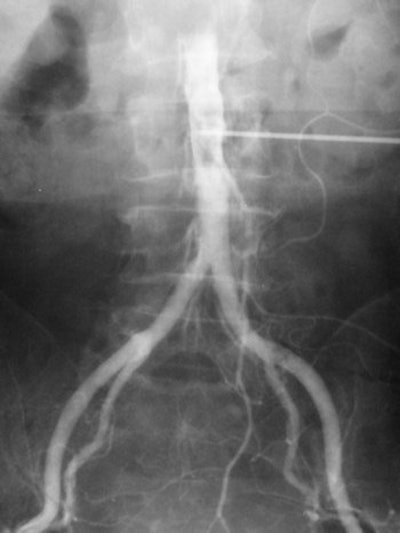

Translumbar aortography

Arteriography was developed in the 1920s with vascular injections from a cutdown. In 1923, Berberich and Hirsch introduced strontium bromide into the femoral artery of a living subject and obtained useful images. The idea was not unreasonable because many cadaveric injections had been made even before 1900. The main problems related to what could be injected and its toxicity.

In Portugal, Egas Moniz made carotid injections in 1927, initially with a cutdown and then by needle puncture. In 1927, building on the experience of Moniz, the team of Reynaldo Dos Santos, Augusto Lamas, and Pereira Caldas from Lisbon described direct abdominal aortic injections. Punctures were made into the aorta with a long needle in a variety of positions, including above the celiac trunk, above the kidneys, above the inferior mesenteric artery, and above the origin of the common iliac artery. The contrast used was a 100% solution of pure sodium iodide that was quite toxic. The injection was painful and therefore required anesthesia.

The translumbar aortogram became the standard vascular examination for decades and was routinely performed at Hammersmith Hospital in London when I started there as a radiology registrar in 1981, more than 50 years after the procedure was first described. There were surprisingly few complications from the procedure. The examination illustrated below was one I performed in 1982.

Translumbar aortograms like this one used to be the standard vascular exam. All images courtesy of Dr. Adrian Thomas.Translumbar arteriography was replaced by catheter angiography from either the femoral or brachial/radial route. Now diagnostic angiography has been superseded by noninvasive imaging such as Doppler ultrasound and also CT and MR angiography. Angiography is now reserved for access for interventional procedures.